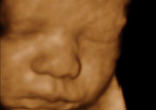

The Defense of Human Life Act recognizes that every human being is a person in the State of North Dakota, and that every person has certain ... continue reading